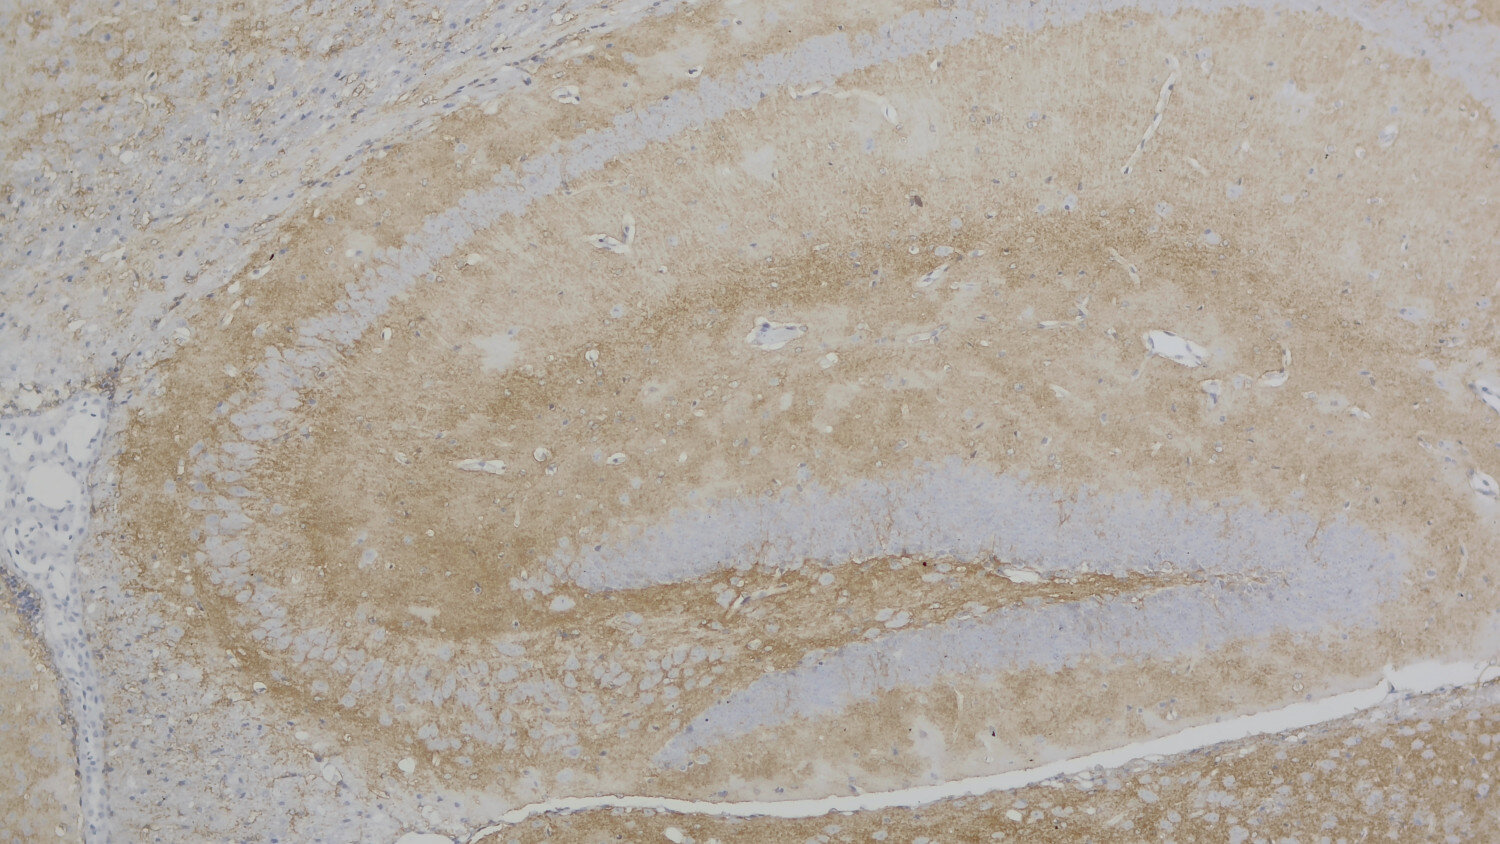

IHC: 1 : 500 gallery

IHC-P (FFPE): 1 : 500 gallery

Immunohistochemistry (IHC-P) of formalin fixed, paraffin embedded (FFPE) tissue (some antibodies require special antigen retrieval steps, please refer to the ”Remarks” section). Immunoreactivity is usually revealed by fluorescence or a chromogenic substrate.